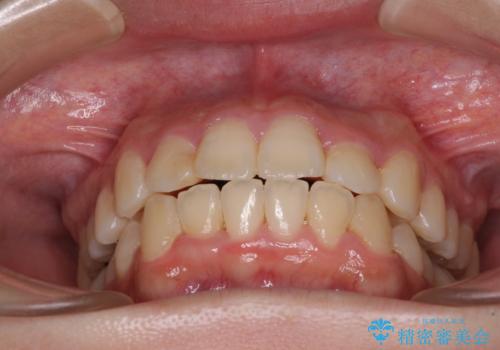

- 上下のデコボコと前歯のクロスバイトを改善したいとのことで来院された患者様です。

極力短期間で治療したいとのことで、ワイヤー装置による矯正治療を行うこととしました。

マウスピースによる矯正治療も提案しましたが、ご自身でのマウスピースの管理の面倒くささと、なるべく早く治療を終えたいとのことで、ワイヤー矯正を選択されました。